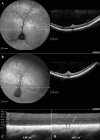

Autosomal recessive retinal degenerative diseases cause visual impairment and blindness in both humans and dogs. Currently, no standard treatment is available, but pioneering gene therapy-based canine models have been instrumental for clinical trials in humans. To study a novel form of retinal degeneration in Labrador retriever dogs with clinical signs indicating cone and rod degeneration, we used whole-genome sequencing of an affected sib-pair and their unaffected parents. A frameshift insertion in the ATP binding cassette subfamily A member 4 (ABCA4) gene (c.4176insC), leading to a premature stop codon in exon 28 (p.F1393Lfs*1395), was identified. In contrast to unaffected dogs, no full-length ABCA4 protein was detected in the retina of an affected dog. The ABCA4 gene encodes a membrane transporter protein localized in the outer segments of rod and cone photoreceptors. In humans, the ABCA4 gene is associated with Stargardt disease (STGD), an autosomal recessive retinal degeneration leading to central visual impairment. A hallmark of STGD is the accumulation of lipofuscin deposits in the retinal pigment epithelium (RPE). The discovery of a canine homozygous ABCA4 loss-of-function mutation may advance the development of dog as a large animal model for human STGD.